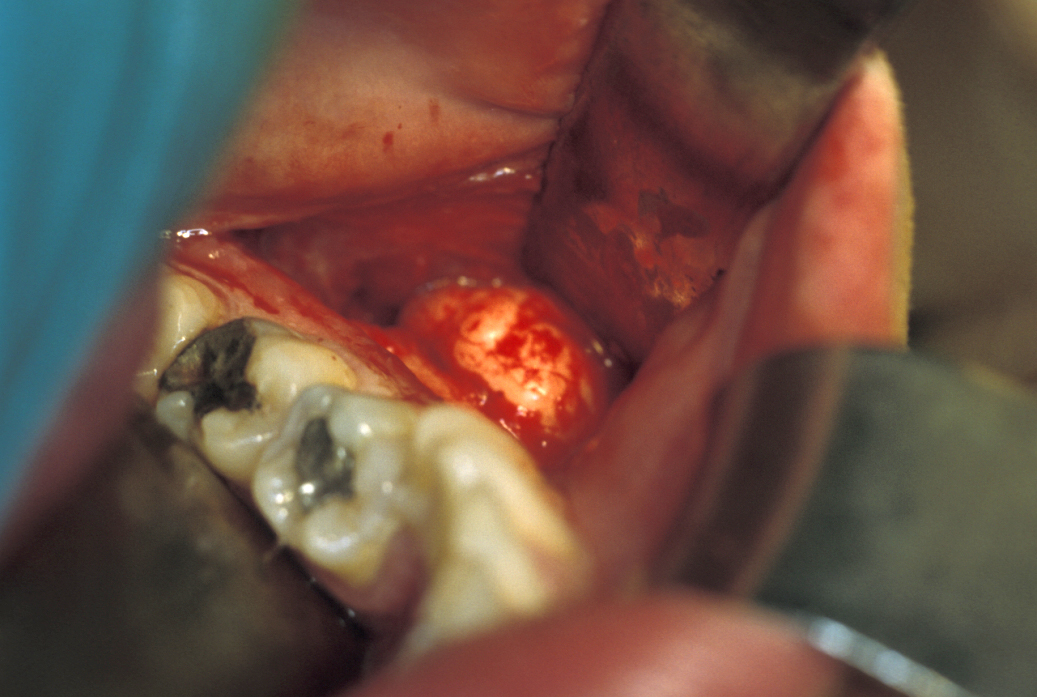

Dry socket (alveolar osteitis)

The treatment of localised dry socket (alveolar osteitis) consists mainly of local treatments. If the application of local anaesthetics can be tolerated, then cleaning out of the socket and dressing it with a resorbable commercial antiseptic or analgesic pack will often be all that is needed. If these packs do not work, then an alternative pack made up of cotton wool, a small amount of zinc oxide (an effective topical anti-inflammatory agent) and eugenol (the main component of clove oil) will provide pain relief. This pack will have to be removed and sometimes has to be replaced, but it is almost unique in providing complete pain relief from intractable dry socket pain.